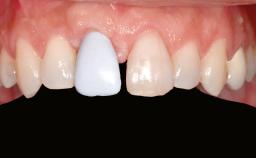

A 20-year-old woman was referred for implant therapy in 2004. Her medical history revealed no significant findings, and neither did she smoke nor take any medications. An extraoral examination revealed no abnormalities of the skin, hair or nails. The intraoral examination revealed only 11 permanent teeth clinically. These were normal in shape, size, and color. In addition, eight retained deciduous teeth (53, 62, 63, 71, 72, 73, 81, 82) were present. No abnormalities were detected during the general examination. The family history revealed that the patient’s father and two sisters were on record with similar conditions. The clinical examination revealed a thick gingival biotype. No recession of the attached gingiva was noted, but the retained deciduous teeth were mobile and unsightly. As a syndrome had not been diagnosed, the case was categorized as non-syndromic oligodontia.